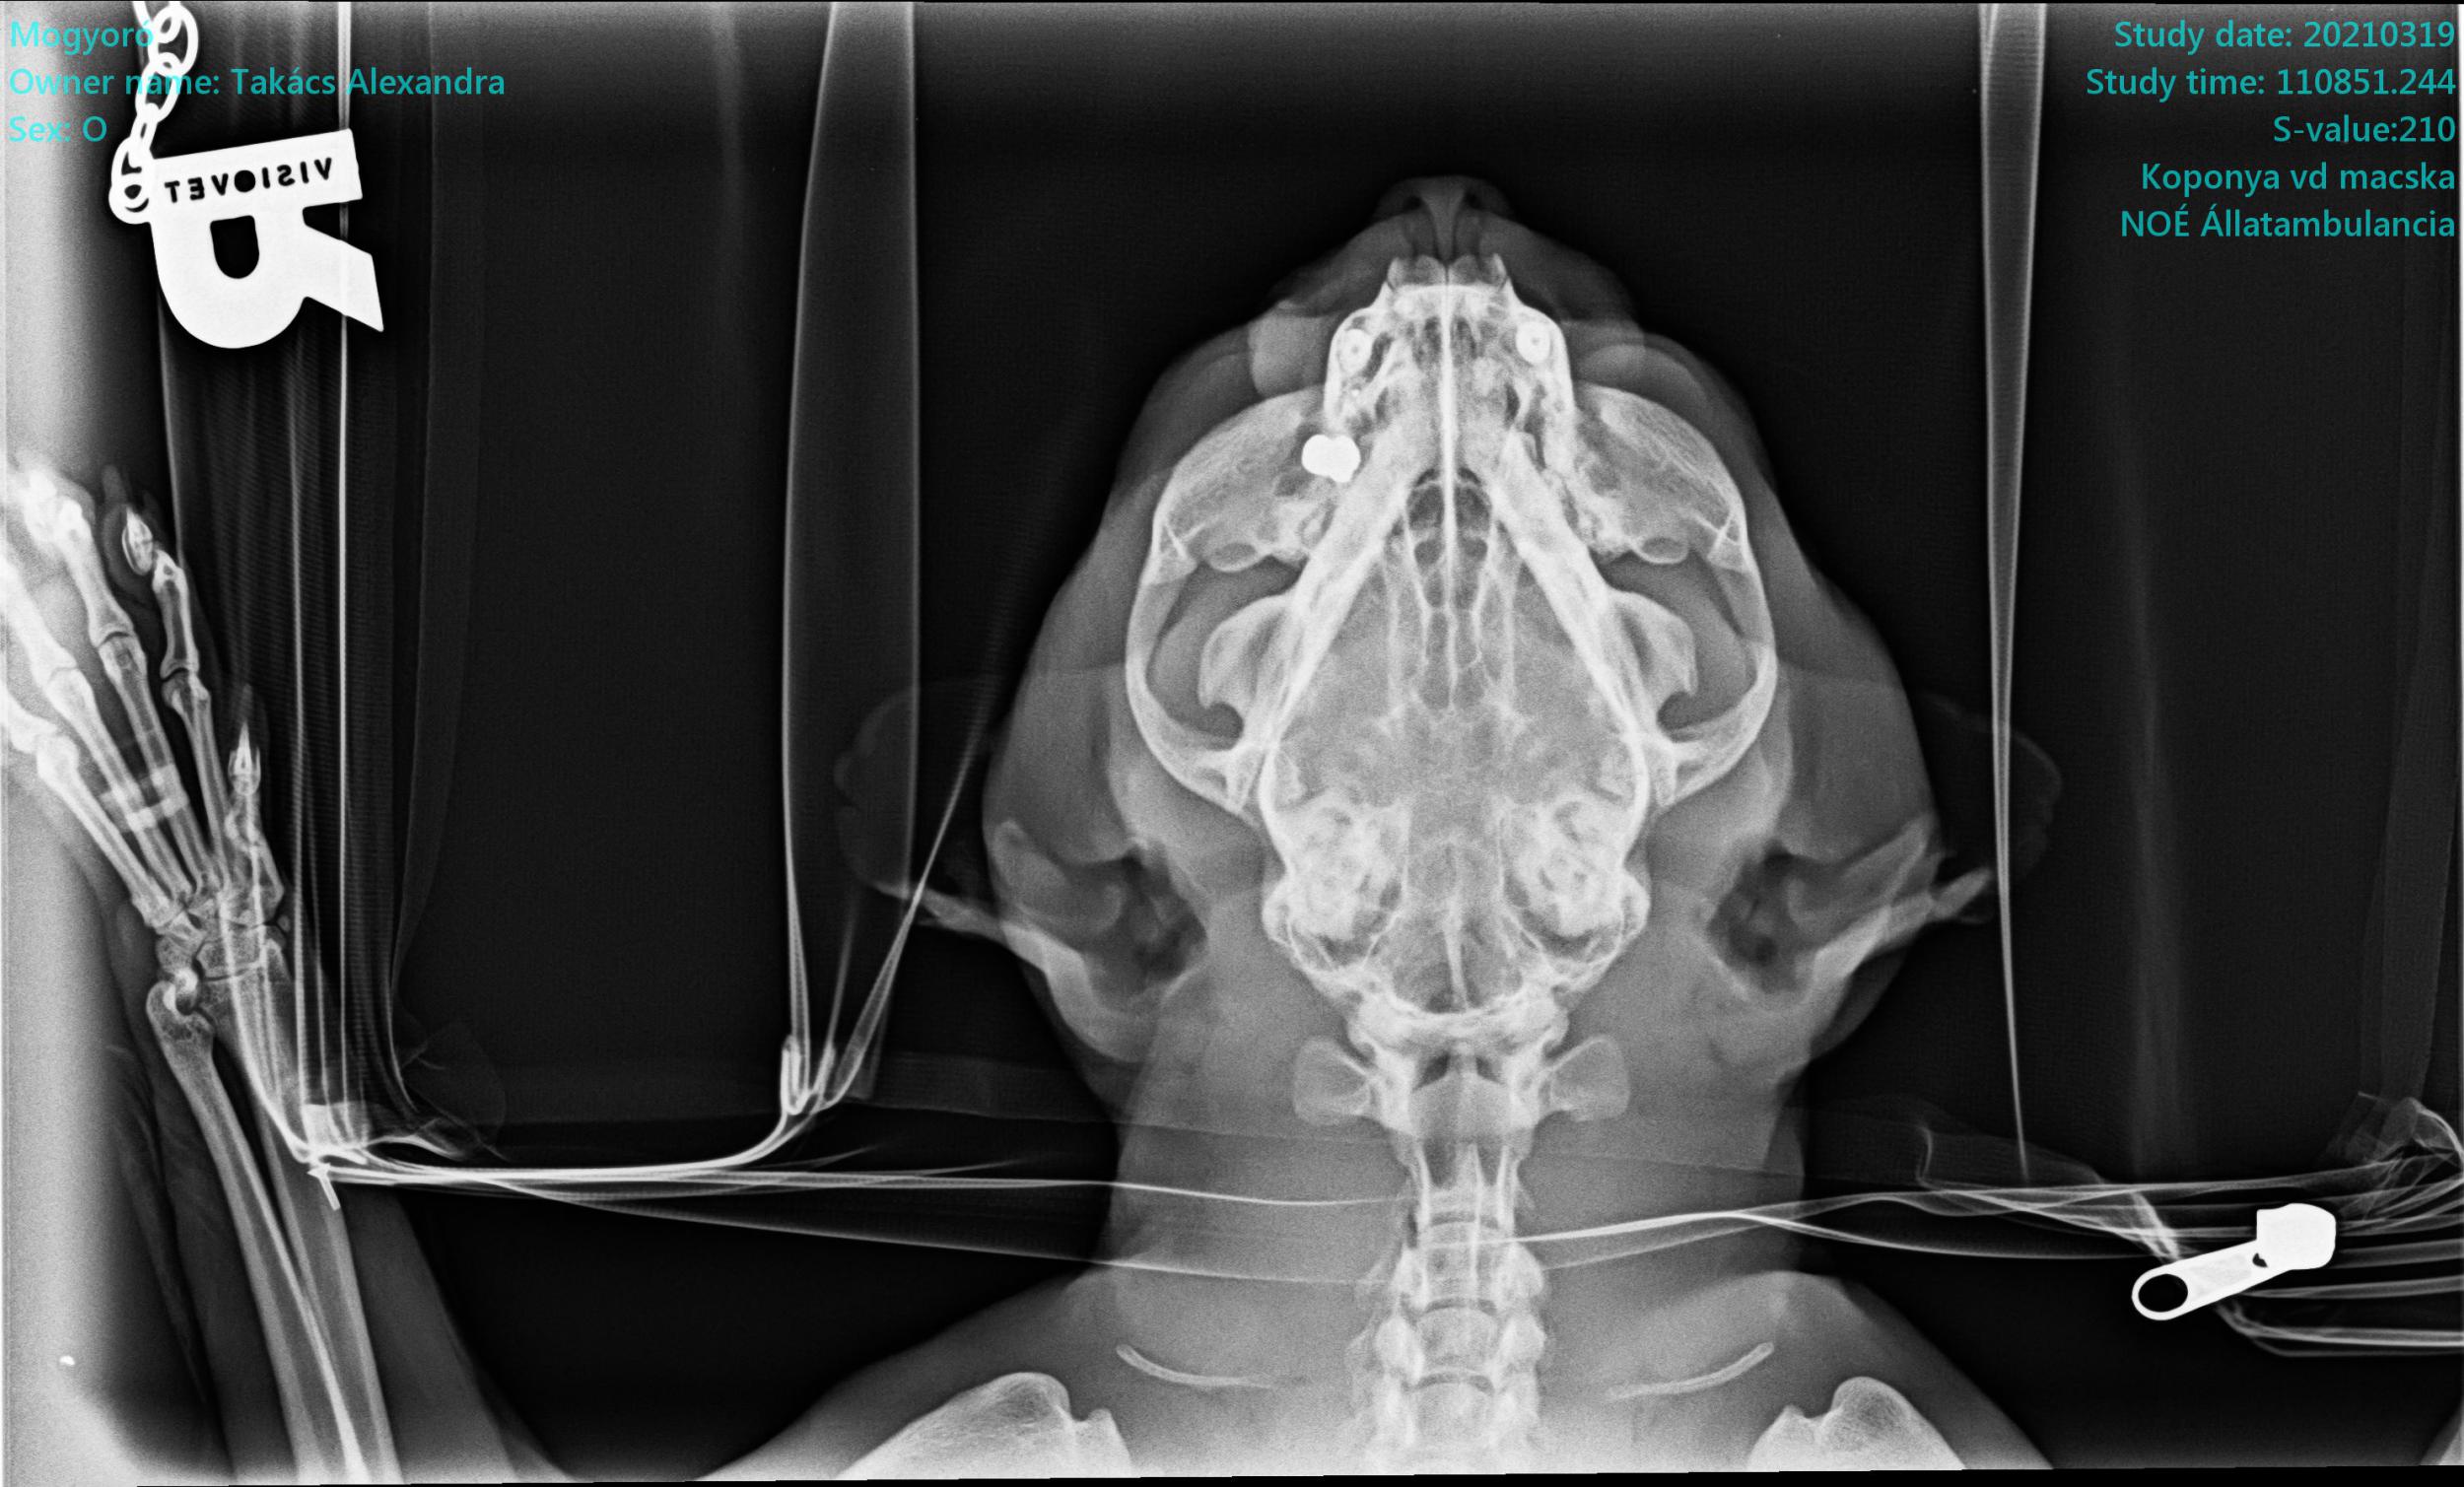

„Aznap még nem tudták megröntgenezni a cicát, csak másnap, mert annyira sokkos állapotban volt, hogy nem lehetett elaltatni a röntgenhez. Aztán másik nap megtalálták a golyót a fejében, a szeme és az agya közé volt beékelődve úgy, hogy az orrcsontját teljesen eltörte. Az mondták a rendőrségen, mert tettem feljelentést, hogy közvetlen közelről, 1-1,5 méterről kellett a lövésnek megtörténnie. Közvetlen közelről lőtték meg az állatot” – idézte fel a történteket.

A röntgenfelvételen jól látszik a beékelődött lövedék. Olyan helyen van a golyó, hogy nem operálható. A vizsgálatok során kiderült, hogy a cica hasán is van egy korábbi sérülésnyom, amit szintén légpuska okozhatott, de akkor csak súrolta a golyó az állatot. Mogyoró, a meglőtt macska önálló életet él a környéken, enni rendszeresen hazajön.